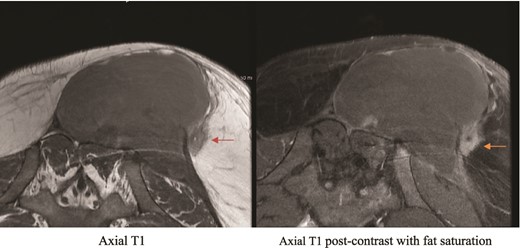

All pathology and culture results were inconclusive, and the patient kept having a drop in Hg, which was managed by blood transfusion. We then proceeded with CT angiogram to delineate the blood supply of the area and to look for possible contrast extravasation, which came back negative. MRI was then requested to rule out soft tissue masses. The MRI result came with unspecific findings but when compared with previous MRI taken in the private hospital, there was slight interval change and a suspicious area, and so interventional radiology were involved to take a deep ultrasonography guided biopsy (Figs 2 and 3).

Private hospital MRI. Axial T1 MRI (left) shows left rounded low T2 signal intensity lesion (orange arrow), which shows hyperenhancement (green arrow) on axial T1 fat saturated postcontrast images (right).